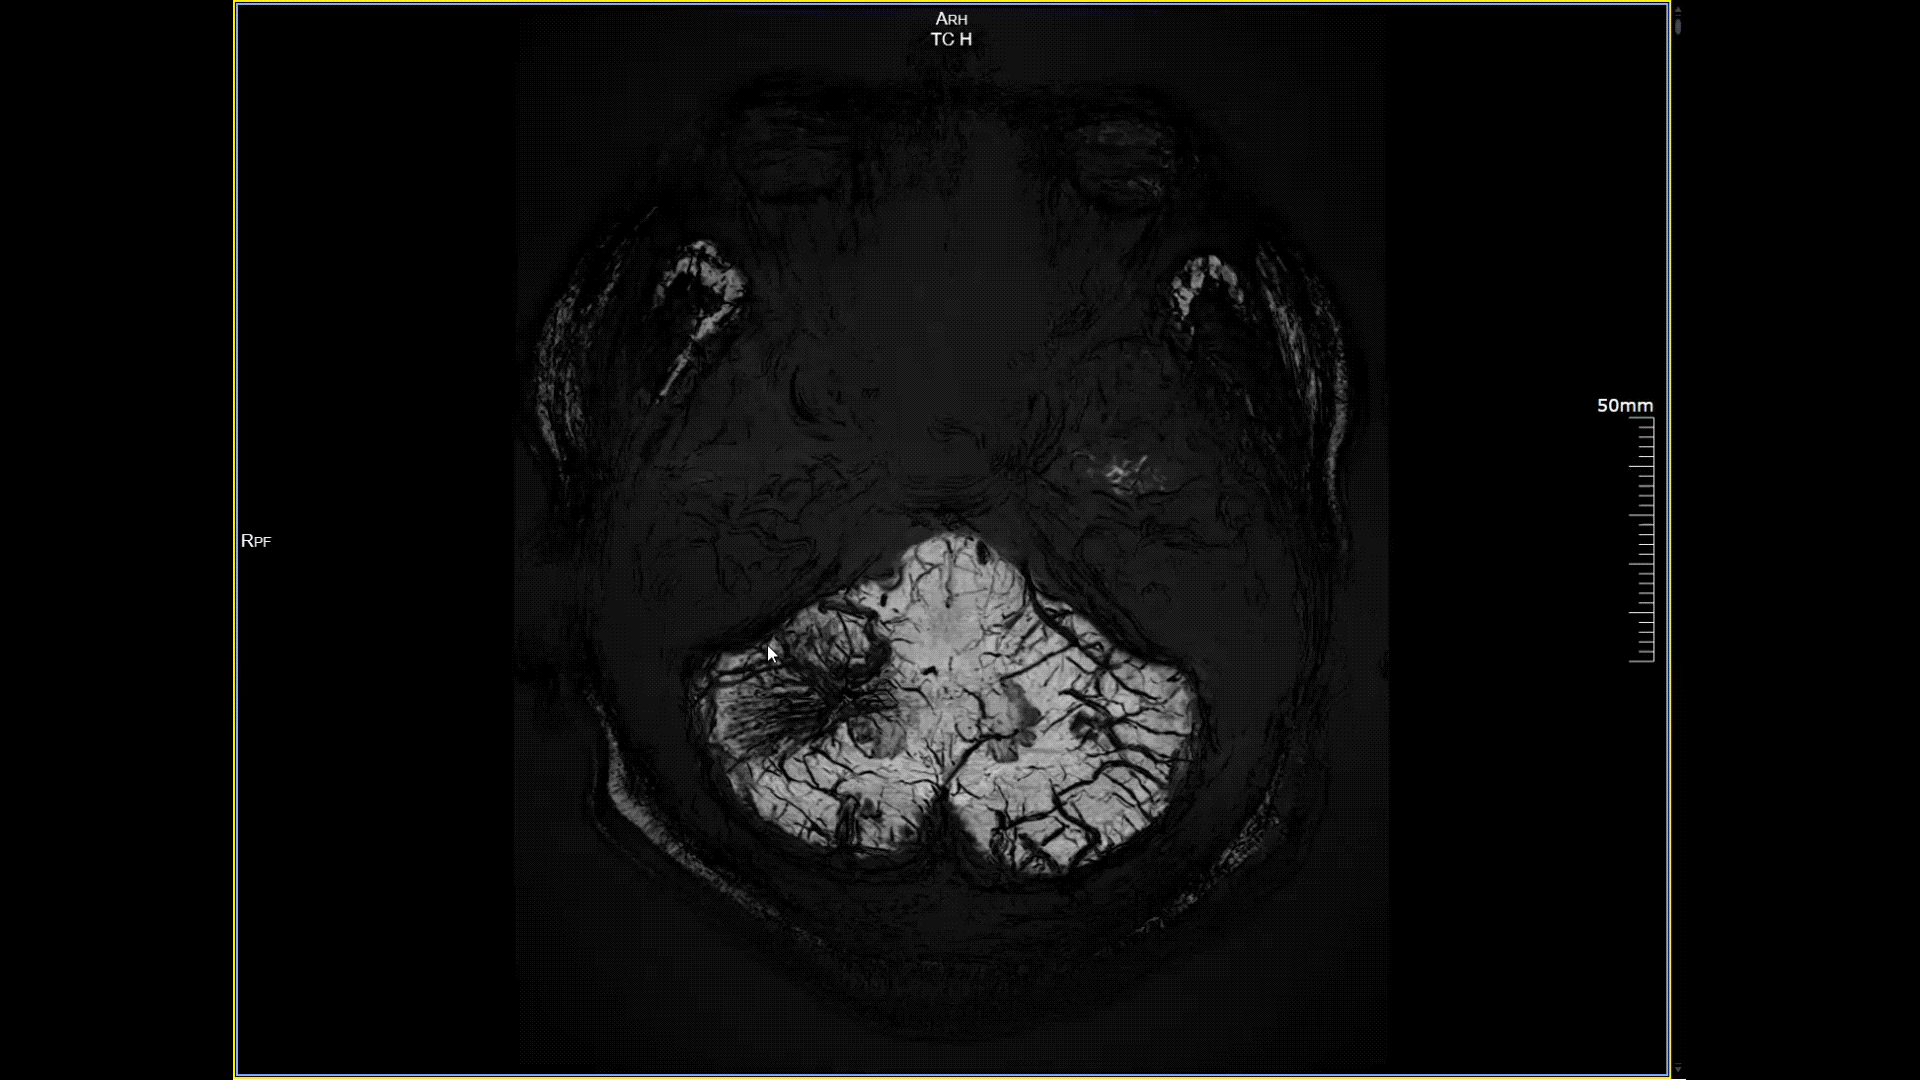

磁敏感成像SWI,分辨率0.2*0.2mm

5.0T磁场强度远高于其他设备,使得氢原子核在磁场中的响应信号极大地增强。这就像在安静的房间里能听清细微的声音一样,高信噪比能让医生看到更微小、更模糊的病变结构。例如上述患者的检查,该设备可以呈现0.2x0.2毫米高分辨率的图像以及动态显示血管走行,使得病变血管的细微解剖结构、分布及其与周边脑组织的关系得以直观呈现,为临床医生进行精准诊断并制定后续治疗方案提供了重要的影像学依据。

11月3日,一名30岁男性在我院接受了河北省首台5.0T超高场核磁共振头颅血管成像检查,图像清晰精准地反映出患者右侧小脑区域的血管畸形情况,该患者对我院的诊疗实力与服务温度给予充分肯定。相较于传统核磁共振,这台设备实现了“超高场全身各部位成像”的技术突破,它以业界领先的超高性能实现亚毫米级超高清成像,尤其在神经、心血管、体腹、关节等部位肿瘤疾病的早期发现、精准评估、个性化治疗方案制定中提供了的强大影像支持,将为全省乃至周边地区患者带来更优质、更精准的医疗服务。